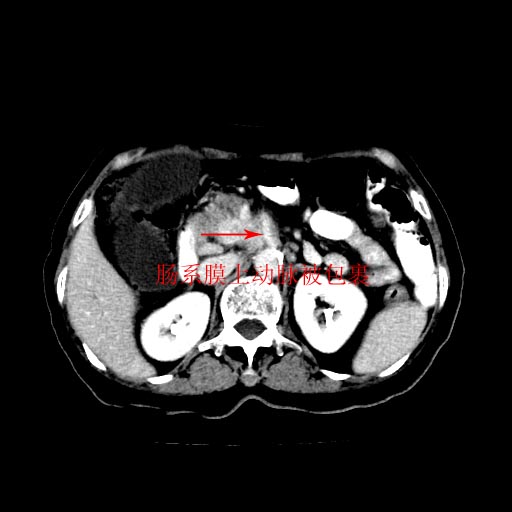

女,74岁,上腹部不适、腹胀两月余,黄染四天。请大家看看肿块周围血管情况。

肝内外胆管及胆囊扩张,胰管扩张,但“双管征”不明显,胆总管下段内见软组织有强化影,肠系膜上静脉推移不是很明显,考虑胆总管下段癌可能大。